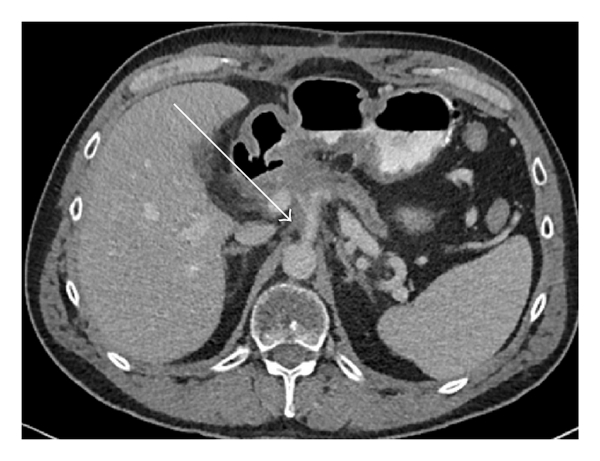

As Figures 1–5 demonstrate, the immediate postablation bed and zone are invariably larger than the original ablated tumor. We remain descriptive because the entire bed was extremely difficult to measure owing to the amorphous, irregular nature of the ablation. Moreover, the ablated tissue is not within an encapsulated organ; therefore, the ablation zone does not have defined borders as seen after, for instance, liver ablation. Four patients that showed continued stable disease are highlighted in Figures 1 through 4. An amorphous, hypoattenuating region with irregular shape persisted in subsequent CT scans in all patients with “stable disease.” Moreover, the ablation zone was typically smaller (due to decreased edema, hyperemia, and granulation tissue) than the immediate postablation bed in the following months and remained stable provided there was no recurrence. Imaging findings demonstrating recurrence are shown in Figure 5. Along with persistent irregular shape the ablation zone showed increased tumor bulk and extension as well as new mass effect (new narrowing of a blood vessel). Enhancement of the ablative bed was variable and often showed increased enhancement in the three-month and longer follow-up images. This was felt to be related to development of granulation tissue and fibrosis.

3.2. Discussion

In our study, we found that the postablation bed is larger in volume than the initial mass. This is expected because it contains the tumor and the ablative margin. The postablation bed and zone appear irregular, amorphous, and hazy without margins or true boundaries. The ablation zone may decrease in size from the initial post-op bed to the initial surveillance study as the surrounding edema/fluid and inflammation resolve revealing the true ablation zone; however, as mentioned above, since there have been reports of an ongoing apoptotic process that persists up to 6–8 weeks after ablation, it will not be unusual to see some increase in volume in surveillance [19, 20]. Therefore, size is considered secondary in the CT evaluation for this reason and because the postablative bed/zone has poorly defined margins, making objective imaging assessment (size, attenuation) cumbersome. This may undoubtedly affect the accuracy and reproducibility of the measurement. Nonetheless, any increase in volume after stabilization of the postablation zone is considered worrisome for recurrence (Figure 5).